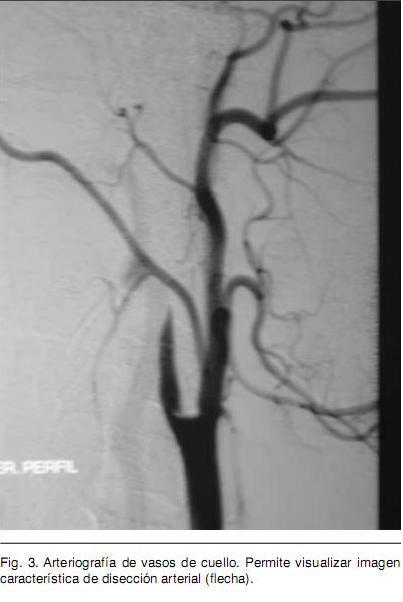

Sexo femenino, 22 años, procedente de medio urbano, diestra, educación primaria completa. Antecedente de migraña de larga data, sin cefalea durante los últimos meses. Destaca en lo ginecobstétrico el consumo de anticonceptivos orales (ACO) combinados y de baja dosis hasta hace tres meses en que se inicia administración de anticonceptivos combinados por vía intramuscular mensual. Dos gestas, dos cesáreas, con nacidos vivos sin complicaciones neonatales; niega historia de aborto espontáneo. Quince días previos a la consulta instala en forma brusca síndrome focal neurológico caracterizado por hemiplejia izquierda total y disartria parética; precediendo al mismo cefalea de predominio en hemicráneo derecho. Se inicia valoración en centro de segundo nivel y se envía en la evolución para completar la misma en centro de referencia. Se realiza Tomografía Computada (TC) de cráneo que informa imagen compatible con ACV isquémico de territorio silviano derecho (Figura 1). Se completa valoración con Resonancia Nuclear Magnética (RNM) que evidencia infarto isquémico en etapa subaguda en territorio superficial y profundo de arteria cerebral media (ACM) derecha, asocia imagen compatible con trombosis de la ACM. El electrocardiograma (ECG) evidencia un ritmo sinusal (Figura 2), con frecuencia de 75 latidos por minuto, P y P-R normales, ventriculografía normal. El Ecocardiograma transtorácico no evidenció alteraciones anatómicas ni trombos en cavidades cardiacas, la Fracción de Eyección del Ventrículo Izquierdo fue de 65%. El Eco Doppler de vasos de cuello informa oclusión de carótida interna derecha de reciente evolución. Arteriografía de cuatro vasos de cuello evidencia disección de carótida interna derecha en el origen y oclusión de ACM derecha en el origen (Figura 3). De la analítica de laboratorio general destaca hemograma, hepatograma, azoemia y creatininemia normales. HIV y VDRL no reactivos. Velocidad de Eritrosedimentación 4 mm en la primera hora. De la valoración de factores de riesgo cardiovascular destaca: Lipidograma con colesterol total de 200 mg/dl, LDL 128 mg/dl y HDL 49 mg/ dl. Glicemia y uricemia normales. Del estudio de la crasis y factores protrombóticos destaca: Tiempo de protrombina de 85%, KPTT 27 segundos, Fibrinógeno 321 mg/dl. Factor V Fig. 1. Tomografía de Cráneo precoz. Destaca imagen compatible con signo de arteria cerebral media hiperdensa (flecha). Fig. 2. Resonancia Nuclear Magnética. Permite valorar imagen compatible con Infarto de territorio superficial y profundo de Arteria Cerebral Media. Fig. 3. Arteriografía de vasos de cuello. Permite visualizar imagen característica de disección arterial (flecha). de Leiden, variante termolábil del gen Metiltetrahidrofolatoreductasa (MTHFR) y FII 20210A, ausentes. Anticuerpos antifosfolipidicos negativo. Del laboratorio de inmunología destaca: Anticuerpos Antinucleares (ANA) 1/40.

Se destaca la importancia de la realización de la arteriografía de vasos de cuello frente al hallazgo de oclusión carotidea en el estudio doppler cervical, lo que permitió arribar al diagnóstico de disección arterial. Confirmada la disección espontánea se continuo con la búsqueda de factores protrombóticos dado la asociación de éstos con DEAC (con y sin trombosis asociada) reportada en la literatura.